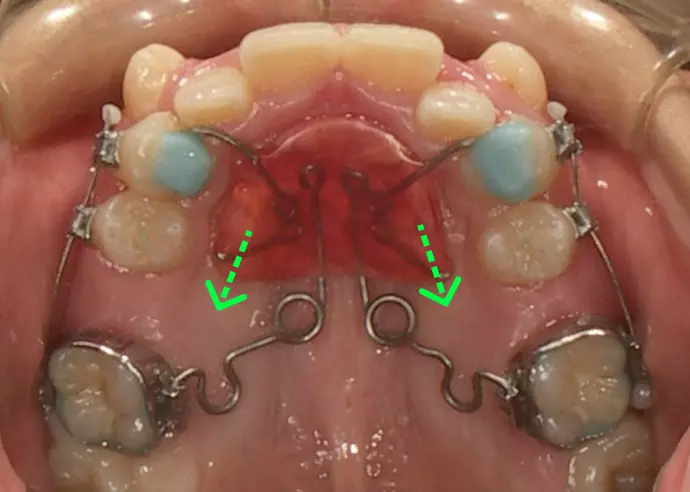

下の歯列を内側の装置で

広げ始めた

下の歯は歯列を横に広げられる(緑の矢印)と判断した。